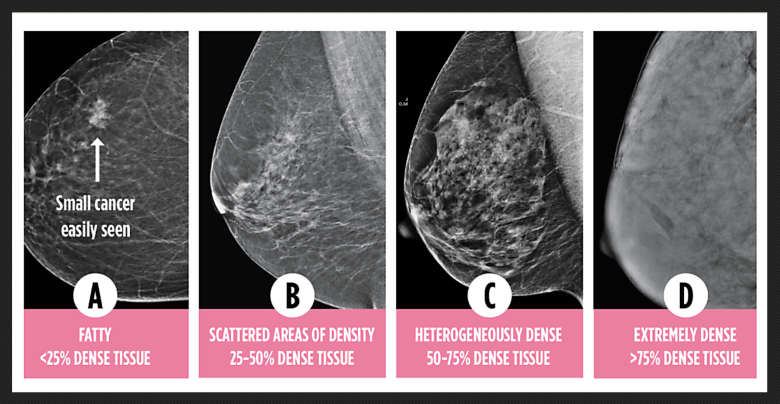

Levels of breast density. Credit: Dense Breasts Canada

Levels of breast density. Credit: Dense Breasts Canada

In a commentary, Jennie Dale, executive director of the non-profit Dense Breasts Canada, writes:

Nearly half of all women who have a mammogram are told they have dense breasts. Dense breasts are common but carry two serious risks: they increase the chance of developing breast cancer and they make cancer harder to detect. On a mammogram, dense tissue and cancer both appear white, creating a masking effect. The result? Cancers are often missed until they grow and spread, leading to more aggressive treatment, higher costs, and worse outcomes.

The good news is that there is a clear, evidence-based solution. Robust research from around the world shows that adding an additional screening test, such as ultrasound, MRI, or contrast-enhanced mammography, significantly improves cancer detection in women with dense breasts. The science is clear: when cancer is found early, survival rates rise dramatically. The five-year survival rate for Stage 1 breast cancer is almost 100%, whereas for Stage 4 it is about 32%.…

That’s why we are urging the provincial government to act now:

Fund supplemental screening (ultrasound, MRI, or contrast-enhanced mammography) for women with dense breasts.

Provide the staff, equipment, and capacity needed so women are not left waiting months or turned away.

Ensure women and healthcare providers receive clear, accurate information about breast density and options for further screening.

Click or tap here to read “Nova Scotia leads country in optimal breast screening practices, but continues to fail women with dense breasts.”